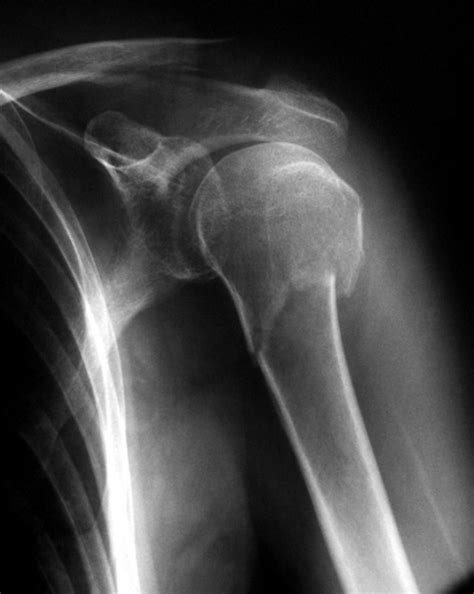

Fractura De Troquiter Sin Desplazamiento Tratamiento, , , , , , , 0, Clínica Traumacor | Traumatólogos Coruña | Fractura de Troquiter, traumacor.es, 906 x 1030, jpeg, WebEn pacientes que han presentado una fractura proximal de hombro sin desplazamiento (pero sin restringir a una rotura aislada del troquiter), sí que hemos. Web¿En qué consiste una fractura trabecular a la altura del troquitier con leve desplazamiento? A finales de octubre tuve un accidente, en primer momento mediante., 20, fractura-de-troquiter-sin-desplazamiento-tratamiento, Novedades y Muebles WebEn pacientes que han presentado una fractura proximal de hombro sin desplazamiento (pero sin restringir a una rotura aislada del troquiter), sí que hemos. Web¿En qué consiste una fractura trabecular a la altura del troquitier con leve desplazamiento? A finales de octubre tuve un accidente, en primer momento mediante.

Web- Con desplazamiento y fractura del cuello quirúrgico sin desplazamiento (dos segmentos) - Con desplazamiento y fractura del cuello quirúrgico con desplazamiento (tres. WebTratamiento en fisioterapia de las fracturas de húmero: Dependiendo del tipo de fractura se optará por tratamiento conservador, inmovilización del brazo con.

WebPara las fracturas conminutas que afectan a la superficie articular, el reemplazo protésico total o parcial parece ser aceptado actualmente como tratamiento de elección 5, sin. WebCuando el dolor y las molestias disminuyen, se recomienda seguir un ejercicios de rehabilitación que te ayude a recuperar la movilidad previa. El tiempo de recuperación. WebEl mecanismo de fractura, el grado de osteoporosis o el trazo de la fractura pueden hacer que la posición natural del húmero se vea alterada en mayor o menor medida. Por. WebCon frecuencia el fragmento desprendido no se desplaza; el pronóstico es bueno y el tratamiento sólo requiere de inmovilizar el brazo en un cabestrillo por 2 a 3. WebEl brazo se inmoviliza para mantener la estabilidad de la fractura y proporcionar alivio del dolor durante la cicatrización. La consolidación de la fractura se. WebEl desplazamiento de los fragmentos casi siempre es moderado y no necesita de ninguna maniobra reductiva. Basta una simple inmovilización con un.